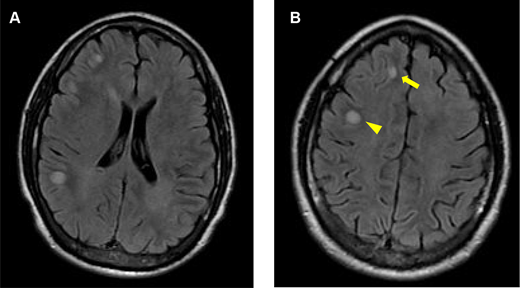

The patient’s magnetic resonance imaging (MRI) of the brain at presentation. A, axial fluid-attenuated inversion recovery (FLAIR) imaging of the brain shows multifocal hyperintensities at the gray–white matter interface. B, axial FLAIR imaging of the brain shows a hyperintense lesion at the right frontal gray–white matter interface (arrow) and a hyperintense lesion in the right frontal white matter (arrowhead).